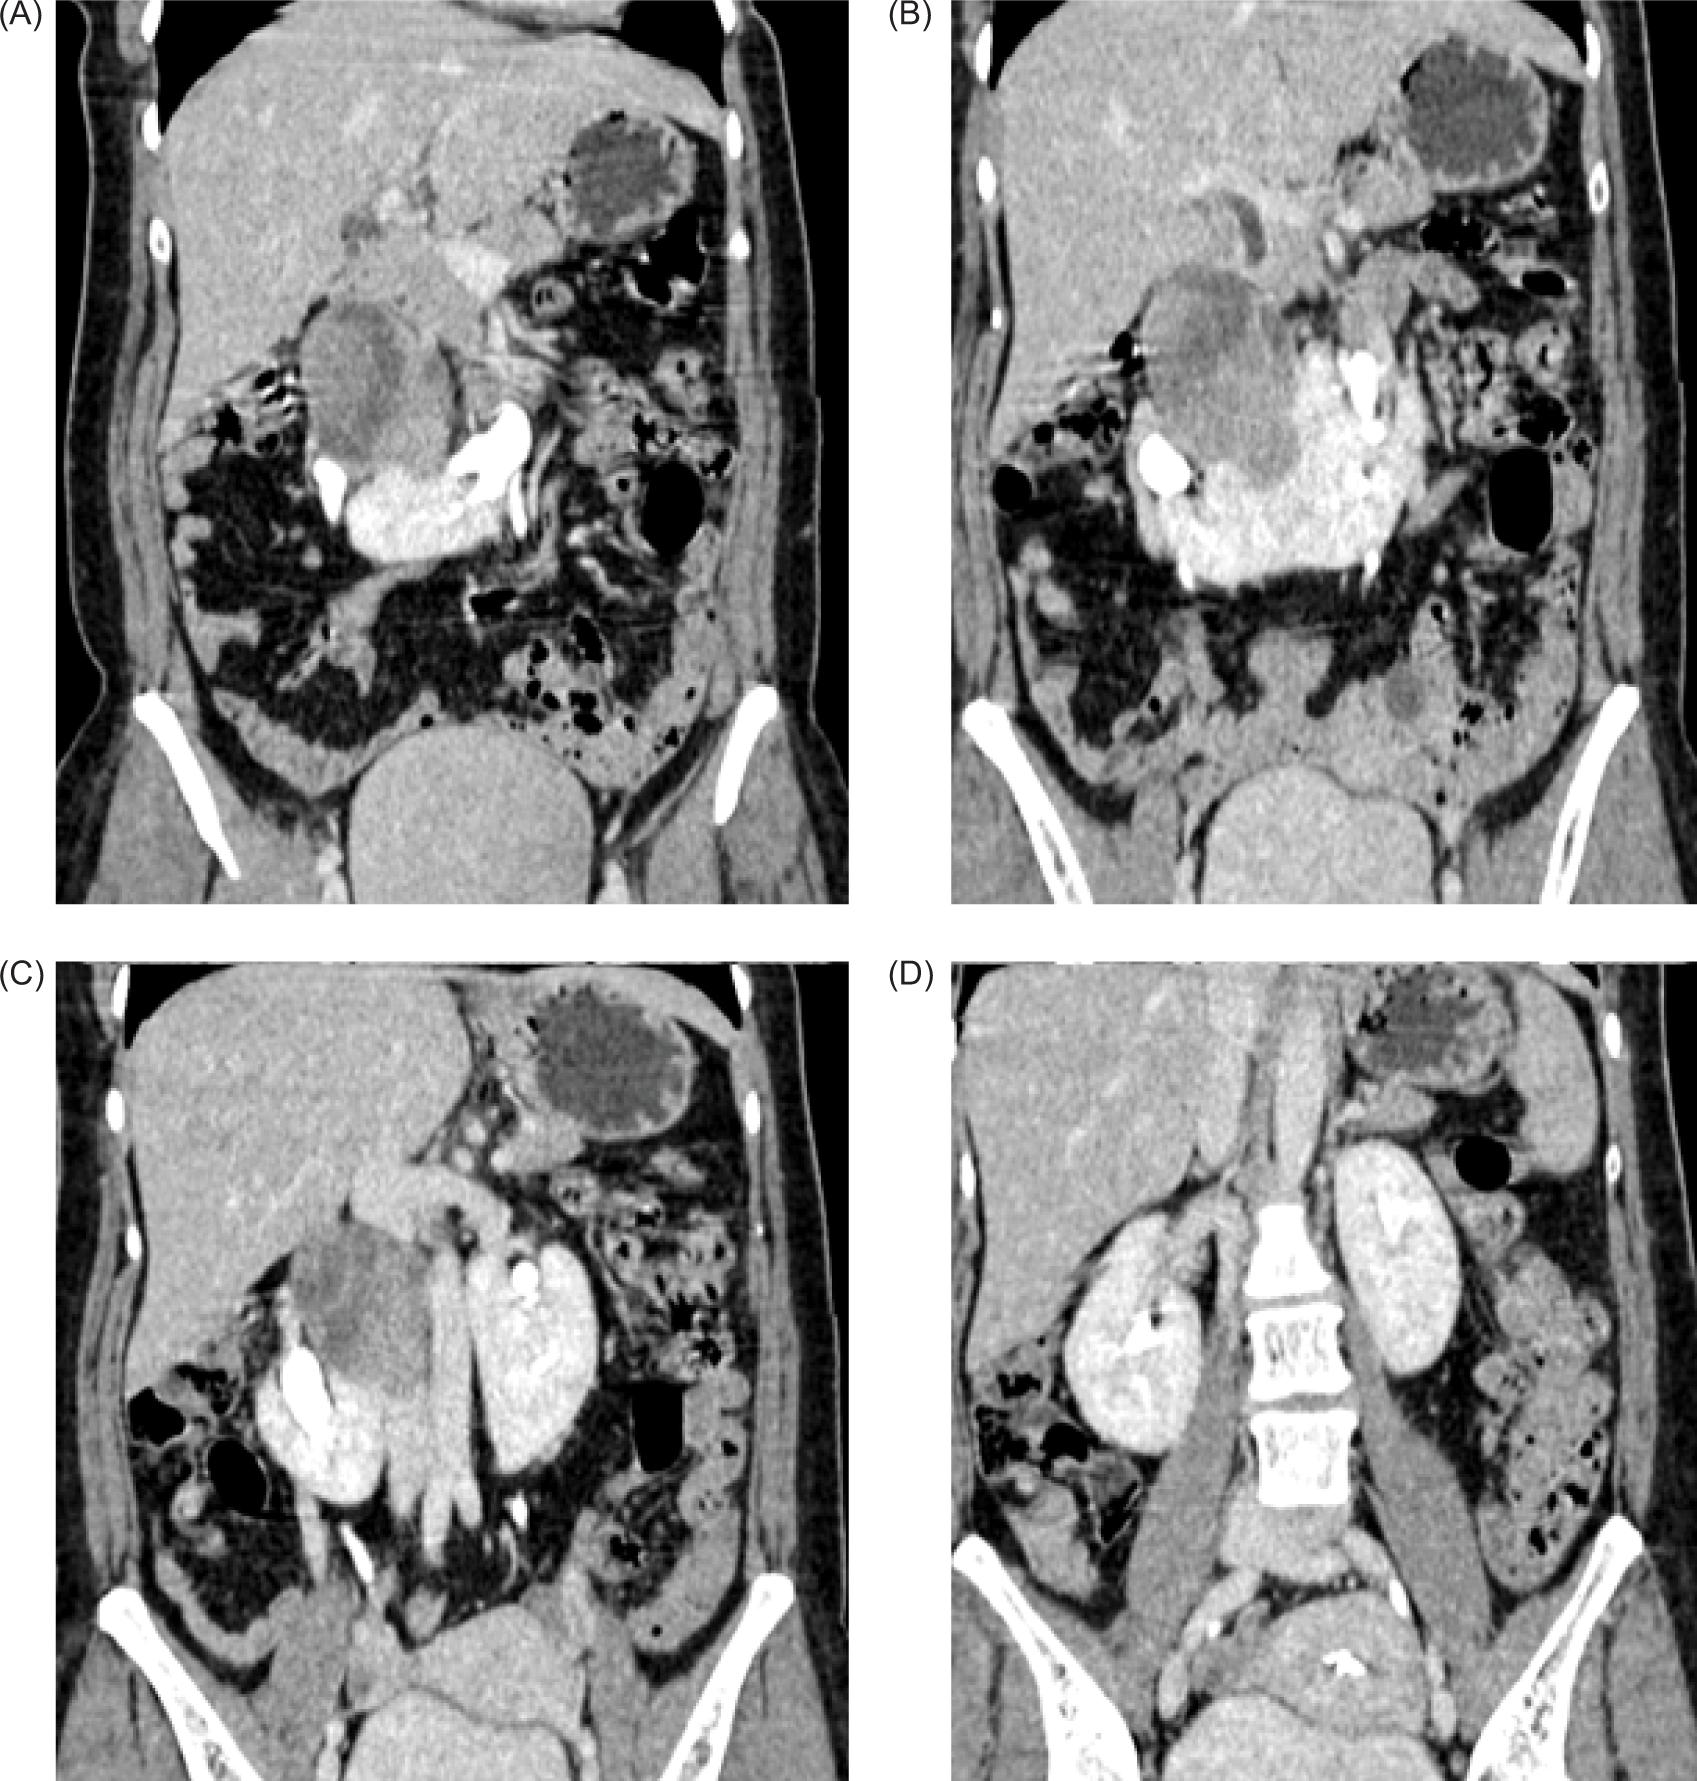

Plain and contrast-enhanced CT scan of abdomen was performed for further evaluation. It revealed HSKs with lower pole of both kidneys deviated medially and fused in midline with renal parenchyma measuring 2.1 cm in thickness and 3.3 cm in cranio-caudal extent. Calyces of lower pole of both kidneys were directed medially. Left kidney showed a bifid renal pelvis. A large, well-defined solid mass of heterogeneous density showing heterogeneous post-contrast enhancement measuring 66 x 54 x 57 mm (transverse x anteroposterior x craniocaudal, respectively) was noted arising from the superior portion of isthmus and extending superiorly at adjoining retroperitoneum and abutting medial surface of right kidney up to renal hilum with obscuration of intervening fat plane. It was extending anterior to right renal hilum and abutting anterosuperior surface of right renal pelvis (Figure 2).

Figure 2: Contrast-enhanced CT coronal sections showing medially deviated lower poles of the bilateral kidneys with heterogenous enhancing mass arising from the superior portion of isthmus of the HSK abutting the hilum of right kidney.